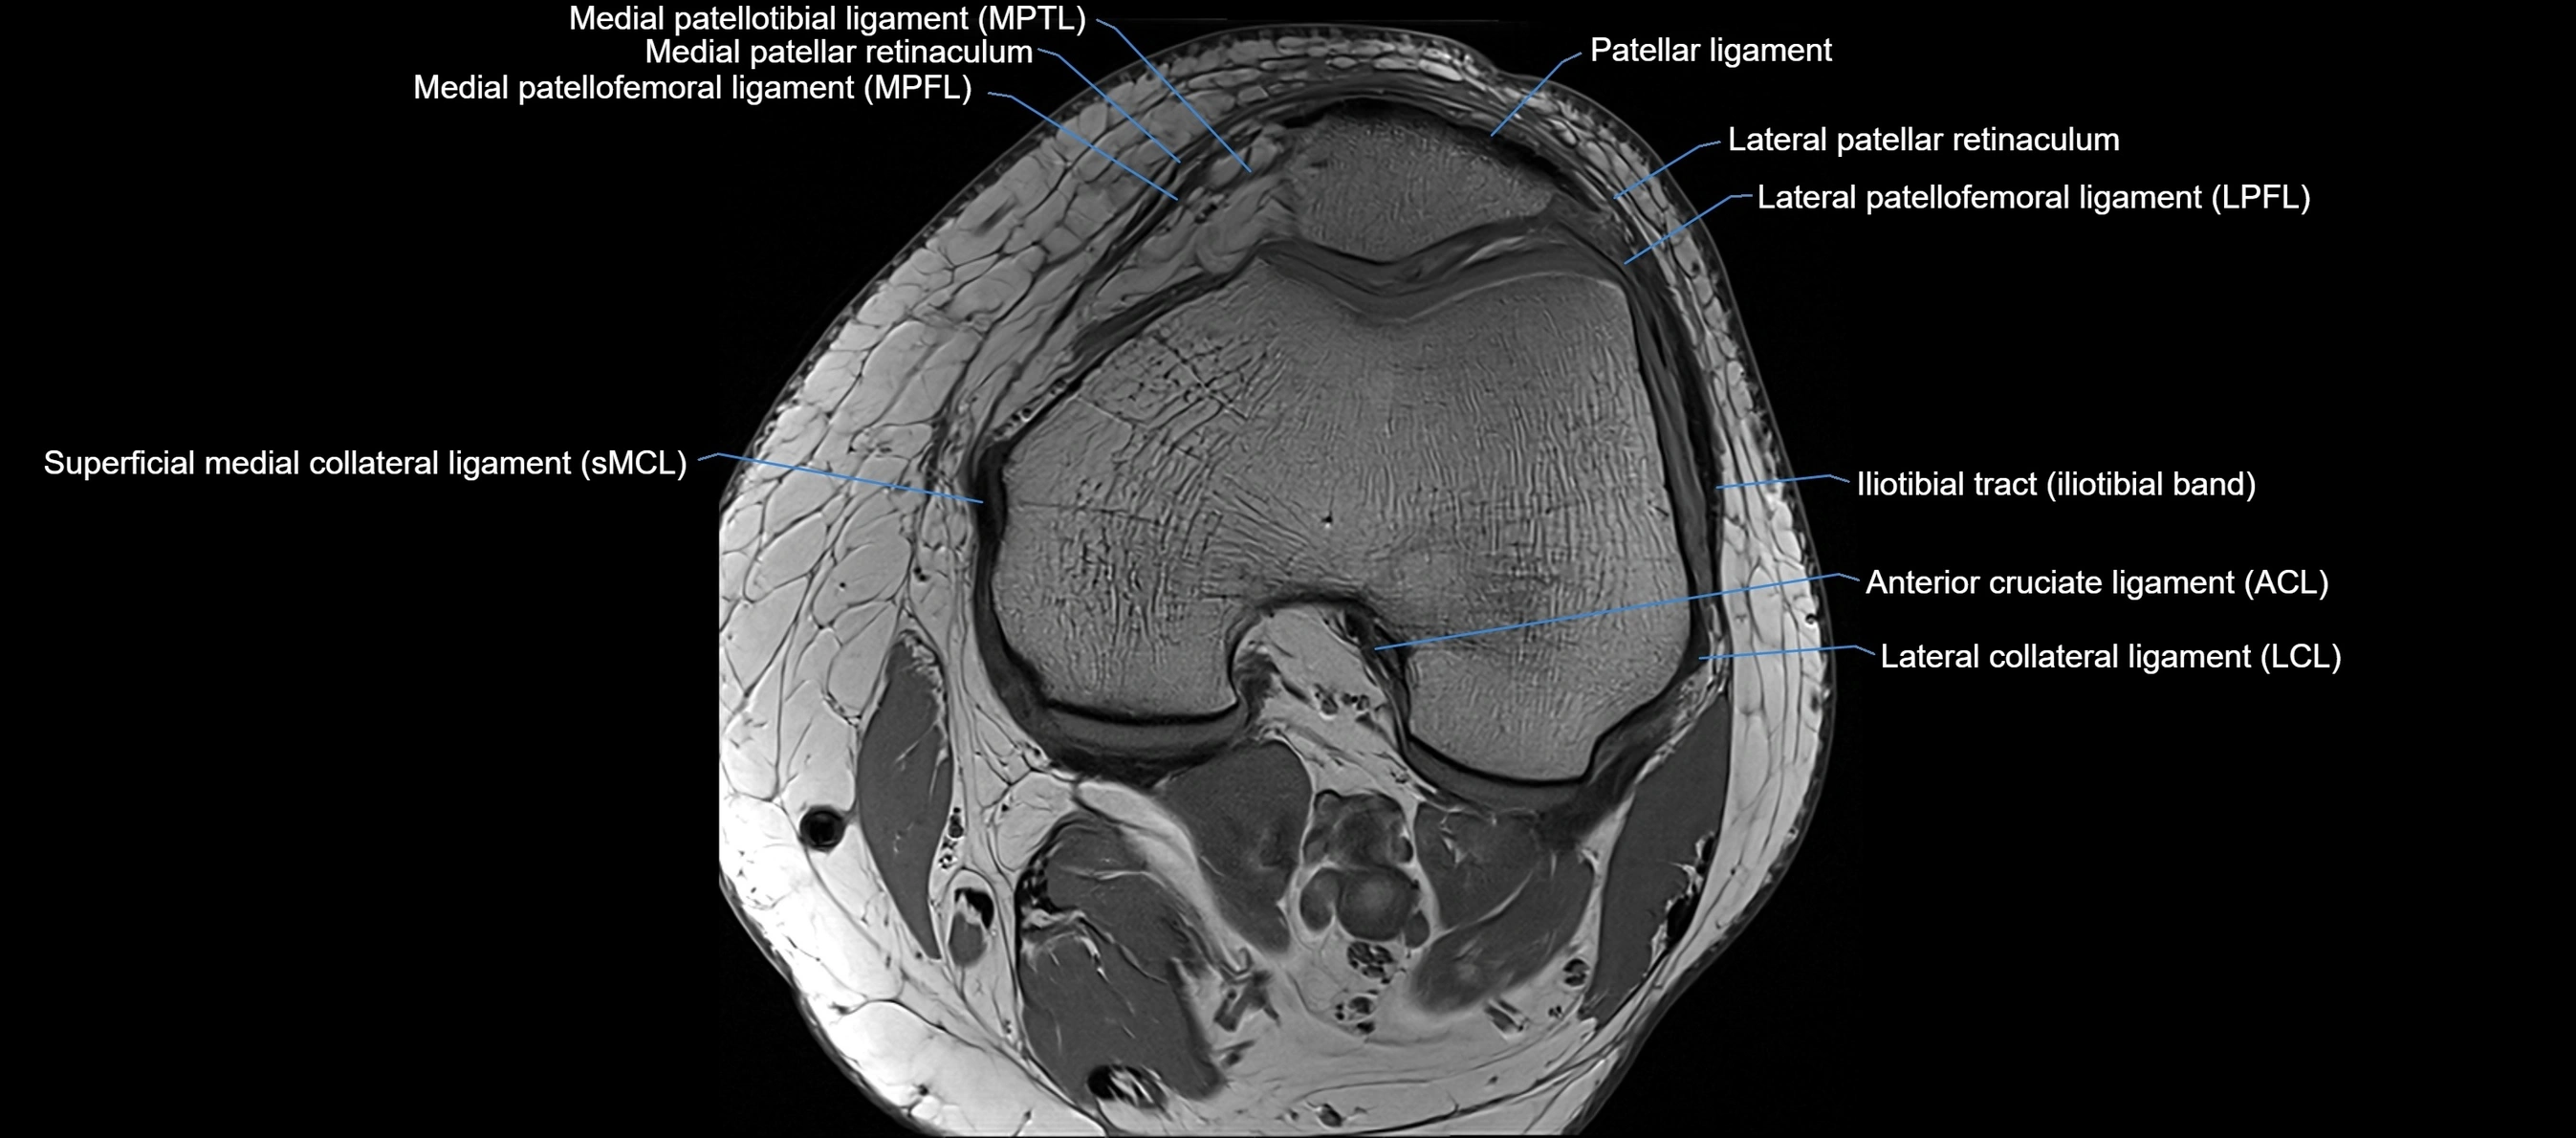

MRI images

image